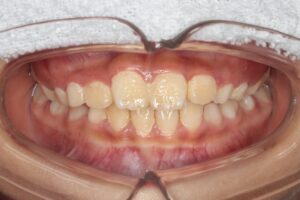

反対咬合(受け口)の症例

Before |

Before